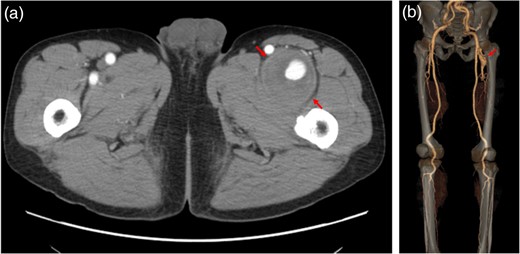

A 58-year-old man presented with paralysis and pain in the left leg, and a mass was found in his thigh. Because of the growth of the mass and the worsening of his symptoms, the patient visited a neighboring hospital. Computed tomography confirmed the presence of a femoral arterial aneurysm. He visited our hospital for more detailed examinations and medical treatment. Physical examination revealed a pulsatile mass with a diameter of 8 cm in the left thigh. The patient had no history of trauma, previous operations or interventions. He had medication-controlled hypertension. Multidetector computed tomography performed in our hospital revealed a large DFA aneurysm with an intraluminal thrombus (Fig. 1). An image diagnosis of a DFA aneurysm was made. There was no evidence of aneurysms or occlusive lesions in the other arteries. Surgical intervention was planned because of the large size of the aneurysm, the high risk of perforation and the worsening symptoms.

Multidetector computed tomography revealed a large DFA aneurysm (arrows show aneurysm).